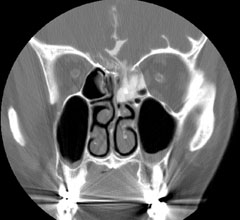

CisternogramCisternograms are used to diagnosis CSF (cerebrospinal fluid) leakage. A CSF leak can occur after trauma and it is often difficult to tell exactly where the location of the leakage is. In order to determine the position of the leak a contrast material is injected into the subarachnoid space via a lumbar approach. The patient is then tilted with the head down and a CT scan is performed to see where the CSF and the contrast is leaking out. A cisternogram can also be performed with a nuclear medicine technique. This is slightly more sensitive, but the anatomic resolution is lower than the CT cisternogram.

Often the two examinations are combined so that both the CT and nuclear contrast materials are injected at the same time. This offers the best anatomic resolution with the highest sensitivity.